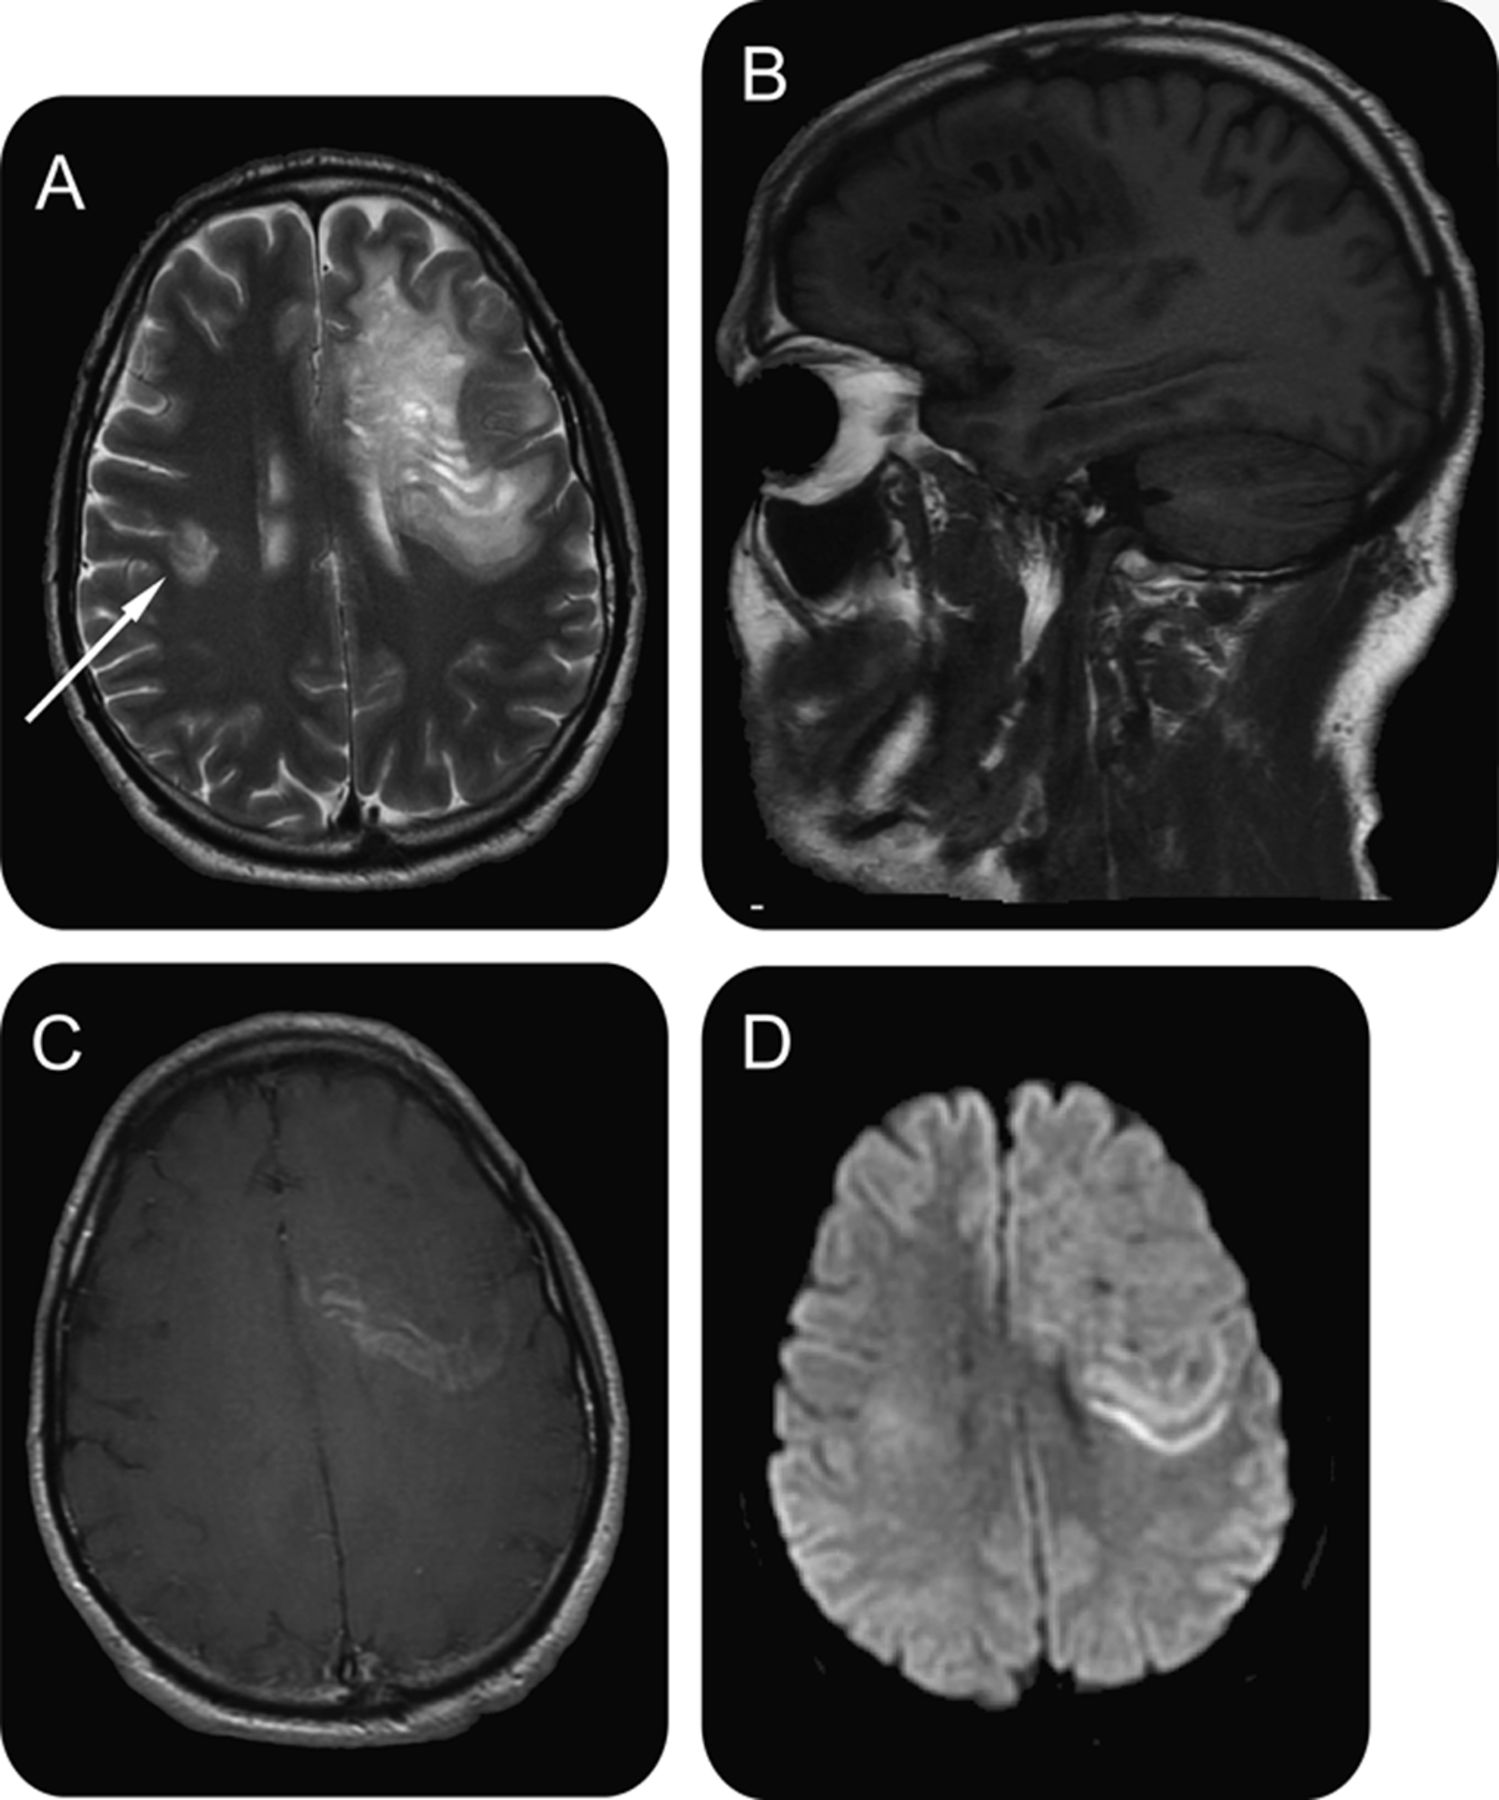

(一)轴向41 t2加权图像。(B)矢状41 t1加权图像。(C)轴向gadolinium-enhanced t1加权图像。(D)轴向diffusion-weighted形象。大左额叶白质病变显示多个T2-hyperintense和T1-hypointense戒指。钆增强和扩散限制出现在最外层(主动)戒指。一个小病变右脑(箭头所指)所示。

一个45岁的男人面对进步布失语症和进行性加重。MRI显示白质病变,多个环(图)。这些离心环反映同心层活跃的髓鞘脱失,典型的Balo同心硬化症。1脑脊液寡克隆乐队和轻微的脑脊液细胞增多。用四甲基强的松龙治疗部分复苏后5天(每天1克)。Balo同心硬化,多发性硬化中罕见的一种,长期以来被认为是一个进步和致命。目前的情况下确认的可能性在某些情况下更良性的课程。2